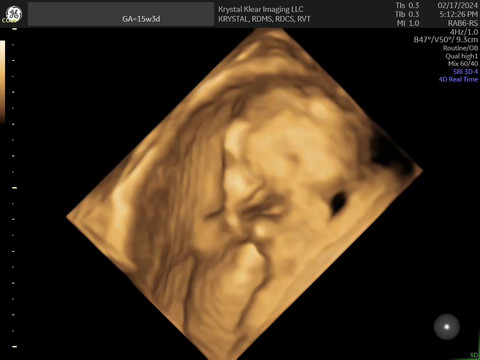

click to view- 15 weeks